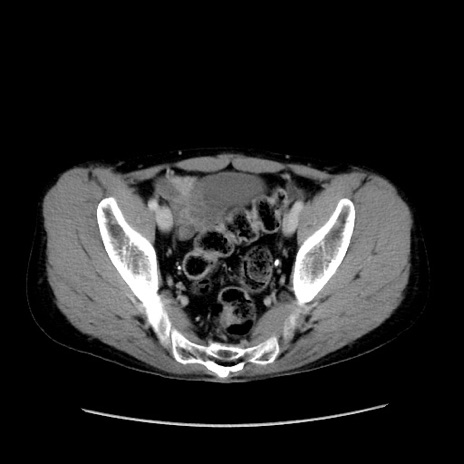

症例37(横断像)

【症例】40歳代 男性

【主訴】腹痛

【現病歴】4時間ほど前に電車に乗車中に臍部上より腹痛出現。徐々に増悪し起立困難となり、救急外来受診。生ものは数日食べていない。今朝お雑煮を食べた。

【身体所見】BT 36.8℃、BP 117/84mmHg、HR 91/min、SpO2 97%、苦悶様、腹部:臍上部広範囲圧痛あり、反跳痛±

【データ】WBC 8100、CRP 0.03